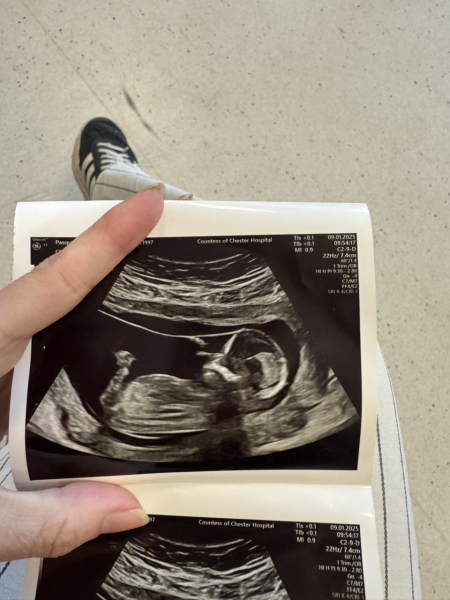

JDecember21 · 09/01/2025 17:01

Hi ladies! Yes went perfectly no issues. The baby was moving soo much it was making me laugh. Took her ages to get the measurements she needed. Very grateful it’s all good. How did yours go?

ps - my scan pic is so clear I can’t believe I can see baby’s face?! Lol

11DPO positive - but concerned